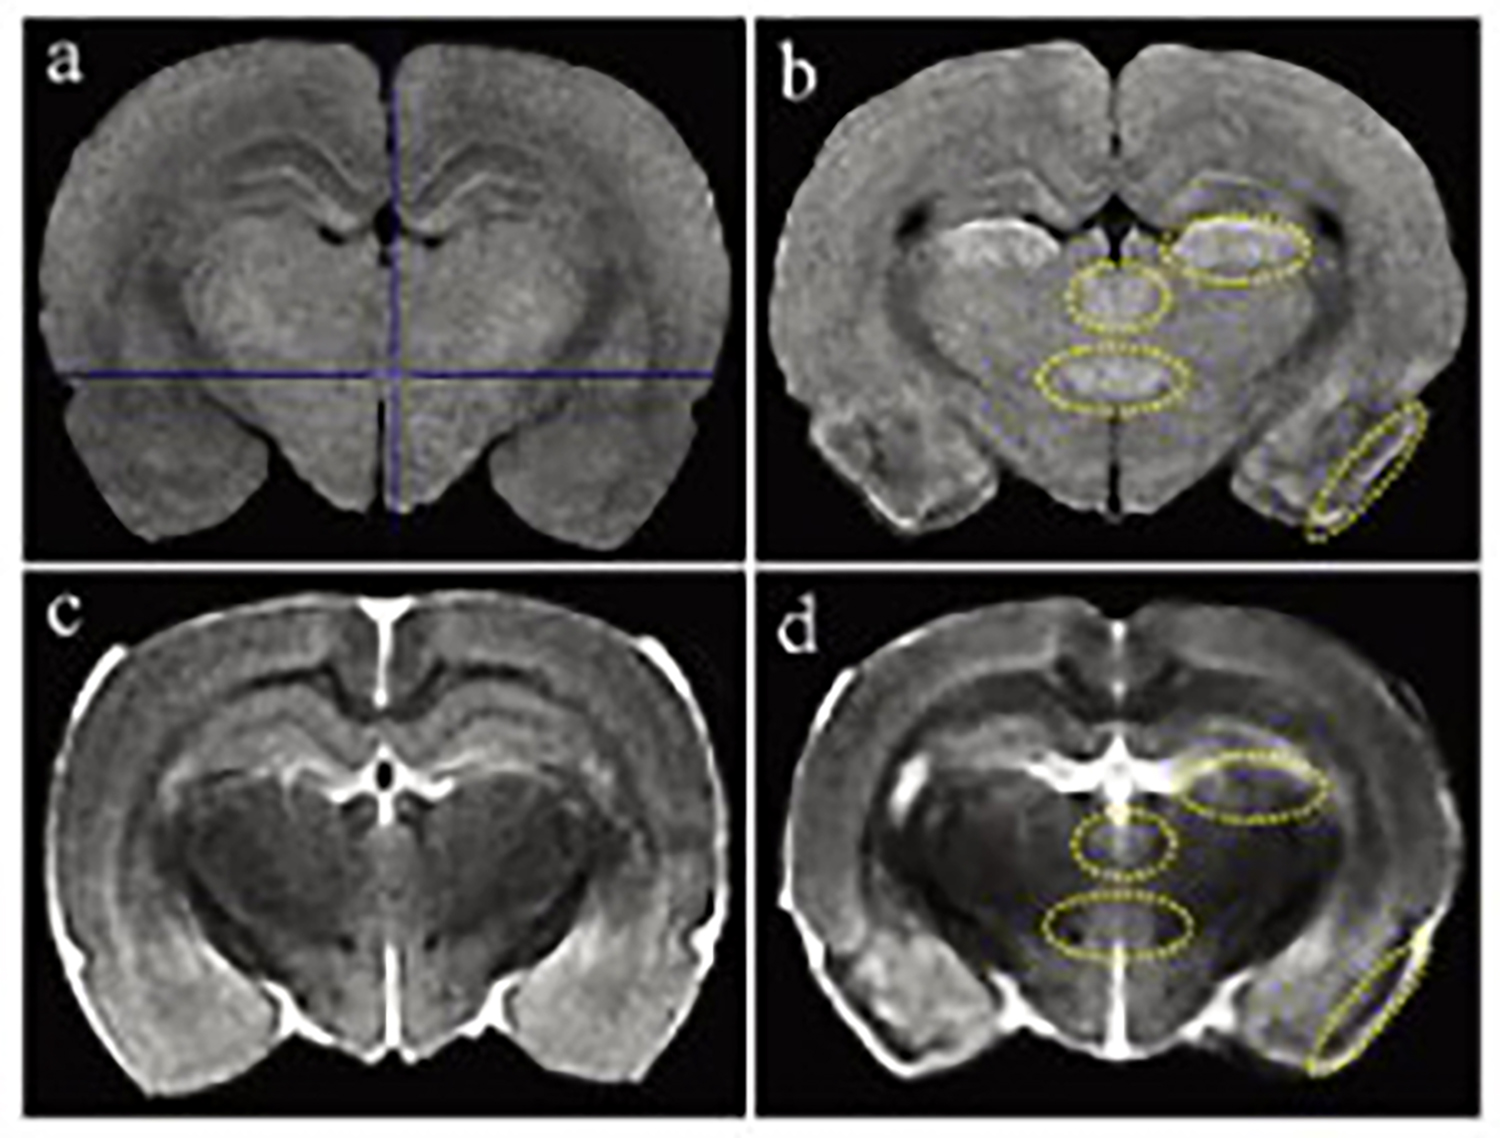

Dixon序列用于大鼠、小鼠水脂分离磁共振成像-脂肪抑制技术

Dixon脂肪抑制技术是由Dixon 提出,其基本原理是利用水、脂肪的化学位移差异,使用不同的回波时问,分别采集水和脂肪质子的in Phase 和 opposed -phase两种回波信号。